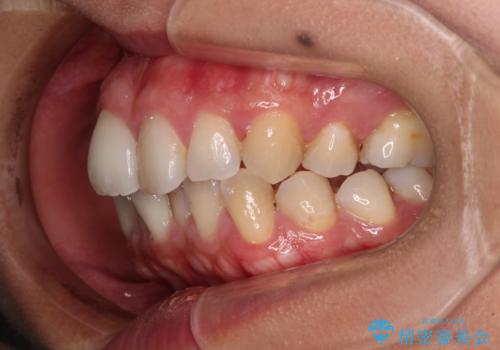

前歯のデコボコを改善 インビザラインの矯正治療

- 前歯のデコボコを治したいとのことで来院された患者様です。

上下顎ともに歯列全体の後方移動とIPR(歯と歯の間を削る)によってデコボコが解消するように設計し、インビザラインにより治療を行うこととしました。

下顎前歯は後戻りを起こしやすいため、舌側を細いワイヤーで固定し、マウスピース型リテーナーで保定を行うこととしました。